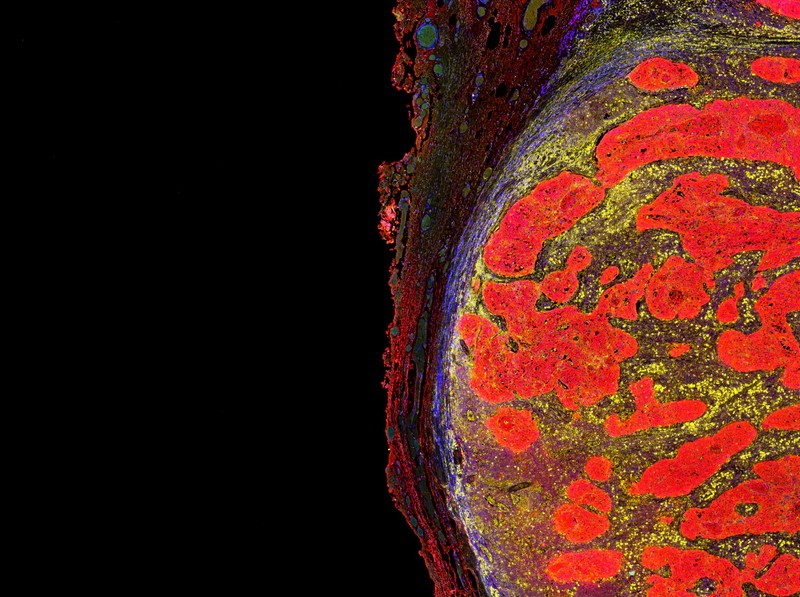

Hideg és forró tumorok: ettől függhet az immunterápiás rákkezelés hatásossága!

Sokan nem reagálnak a terápiára, illetve számos olyan betegnél, aki mégis reagál a kezelésre, végül áttétek képződnek. Egy kutatási eredmény áttörést hozhat ebben.